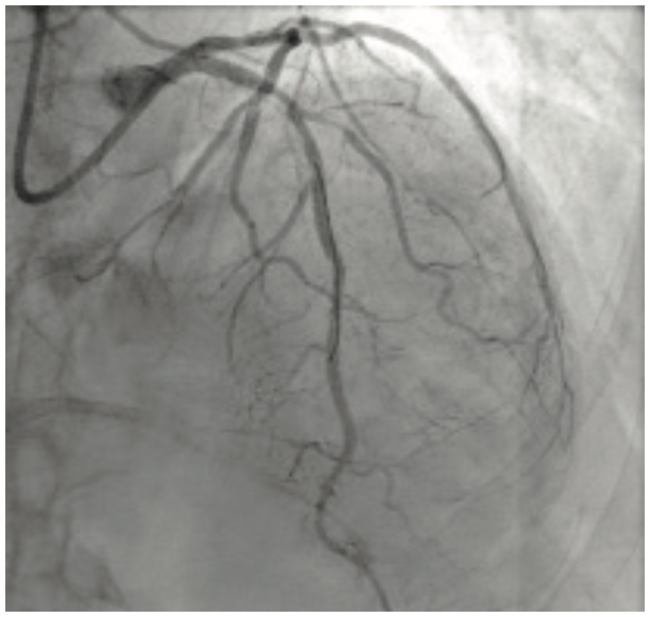

Patient A was a 62-year-old female with a medical history significant for hypertension, hyperlipidemia, former tobacco abuse, vascular dementia yet still living independently, chronic obstructive pulmonary disease, coronary disease status post extensive stenting of the right coronary artery, previously stented subclavian stenosis, and type 2 diabetes, carotid stenosis status post endarterectomy and stenting, and lower extremity peripheral arterial disease, who presented to her primary cardiologist with labile blood pressures and Canadian Cardiovascular Society (CCS) class III angina that was relieved with sublingual nitroglycerin. She was chronically maintained on aspirin 81 mg, clopidogrel 75 mg, metoprolol tartrate 37.5 mg twice daily, ranolazine 1000 mg twice daily, and rosuvastatin 20 mg daily. She had previously trialed isosorbide mononitrate, but could not tolerate it due to headaches. The patient was referred to left heart catheterization without antecedent stress testing. Prior to a previous intervention to her right coronary artery, the patient had been evaluated by our cardiothoracic surgery department for bypass and was thought not to be an acceptable candidate due to vascular dementia, her medical comorbidities, and peripheral arterial disease.